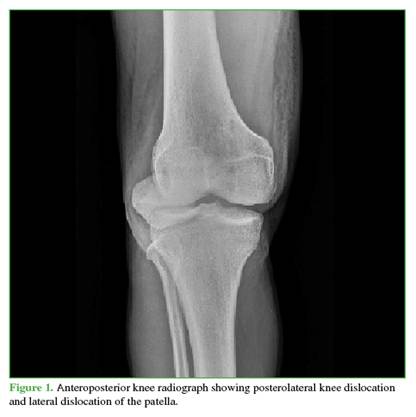

Radiographs showed widening of the medial joint space consistent with medial instability. Further imaging was obtained with magnetic resonance imaging (Figures 4 and 5) to evaluate possible interposed tissues or structures, and with CT angiography (Figure 6) to rule out vascular injury given the time elapsed since trauma. Marked edema was noted in the medial soft tissues, including the capsule and medial structures in the intercondylar region, along with persistent knee subluxation. Vascular compromise was ruled out, with preservation of the femoropopliteal vascular bundle.

Most irreducible knee dislocations are posterolateral. Tibial displacement occurs due to a generally high-energy valgus force with the knee flexed, associated with simultaneous rotational forces on the tibia and femur in opposite directions, which push the medial femoral condyle through the anteromedial capsule and retinaculum. Subsequent interposition of the medial retinaculum, the medial collateral ligament, the vastus medialis, or the medial meniscus can give rise to the “pucker sign” or “dimple sign,” a characteristic finding on physical examination and present in up to 83% of irreducible knee dislocations.12,13

An important aspect of this type of knee dislocation is the involvement of the medial capsuloligamentous complex and its interposition between the femoral condyles during severe valgus stress, which confers its characteristic irreducibility. Early clinical diagnosis and open reduction, with or without arthroscopic debridement, are essential to reduce the risk of soft-tissue compromise in this condition. Prompt restoration of joint congruity, verification of adequate distal perfusion, and exclusion of vascular injury, one of the potential complications, are urgent priorities.14

Fortunately, in this case, no skin complications occurred. However, it is important to note that the dimple sign is a key clinical indicator suggesting irreducibility of the dislocation and the need for timely open reduction, as attempts at closed reduction may cause further skin injury, and delays in diagnosis and treatment may lead to skin necrosis.